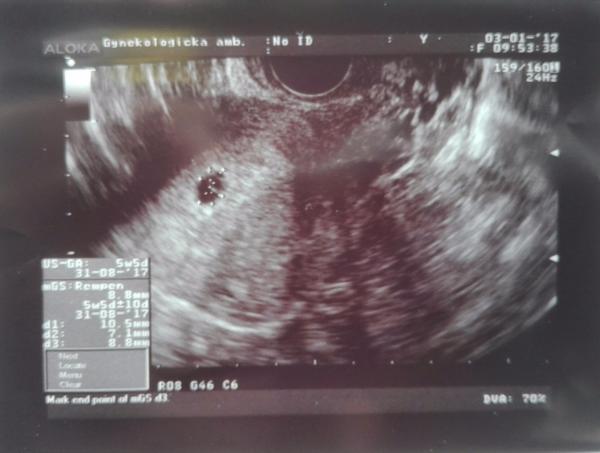

@luta13 dakujem zo ❤ testik z 2.1. a prve foto nasej fazulky.Podla PM som 3.1. bola 6tt+2,ale podla sona 5tt+5.Dr.povedal,ze taka odchylka je este vporiadku.Dalsie sono nas caka 16.1.,ci uz bude srdiecko.Drz nam prosim palce,nech vidime srdiecko krasne bit. 😉